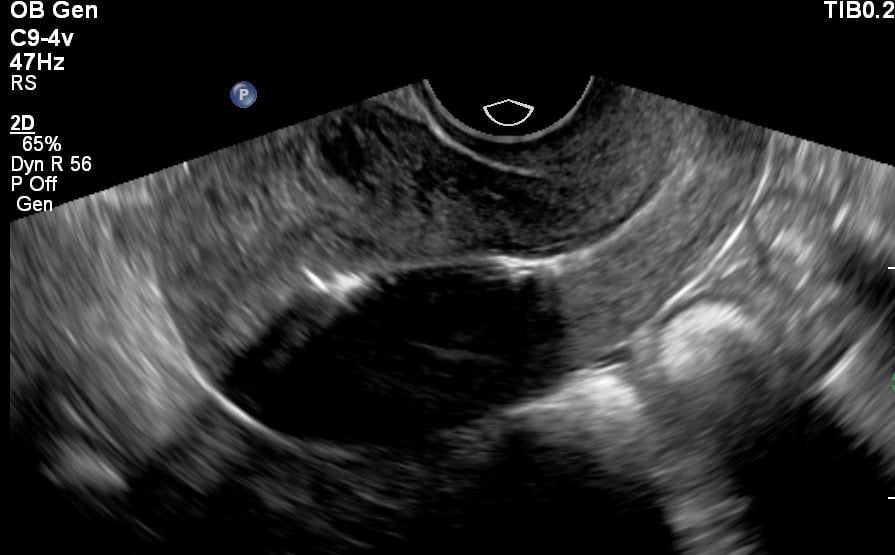

Als je een spiraal geplaatst hebt gekregen bij ons in de praktijk via 040anticonceptie, dan krijg je bij de plaatsing van je spiraaltje en 4-6 weken na plaatsing een echo als je dat wil. We kijken dan of de spiraal op de juiste locatie in je baarmoeder zit, de pootjes goed uitgeklapt zijn en of er geen bijzonderheden te zien zijn bij je eierstokken (ovaria).

Mocht je een spiraal hebben en wat klachten ondervinden, dan kun je ook bij ons terecht voor een controle-echo van je spiraaltje. Ook als de spraal niet door ons eigen team is geplaatst. Soms is het na een paar jaar gewoon fijn om te weten dat alles in orde is. Je kunt de assistente bellen voor een afspraak. Je kunt dan op korte termijn bij ons terecht. De kosten van deze spiraalcontrole echo worden niet altijd vergoed door je verzekeraar. De kosten voor deze echo bedragen € 50,37.